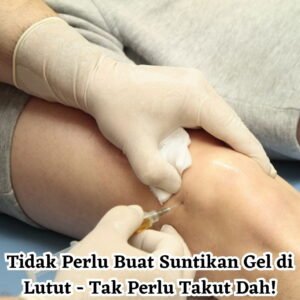

2. Suntikan Steroid Pada Sendi

3. Suntikan Cecair Gel Ke Dalam Lutut

Di Antara Kelima-lima Cara, Produk Sapuan Adalah Cara Paling Mudah Dan Cepat Untuk Merawat Arthritis Dengan Kos Rawatan Yang Jauh Lebih Murah Dan Dalam Jangka Masa Yang Pantas.